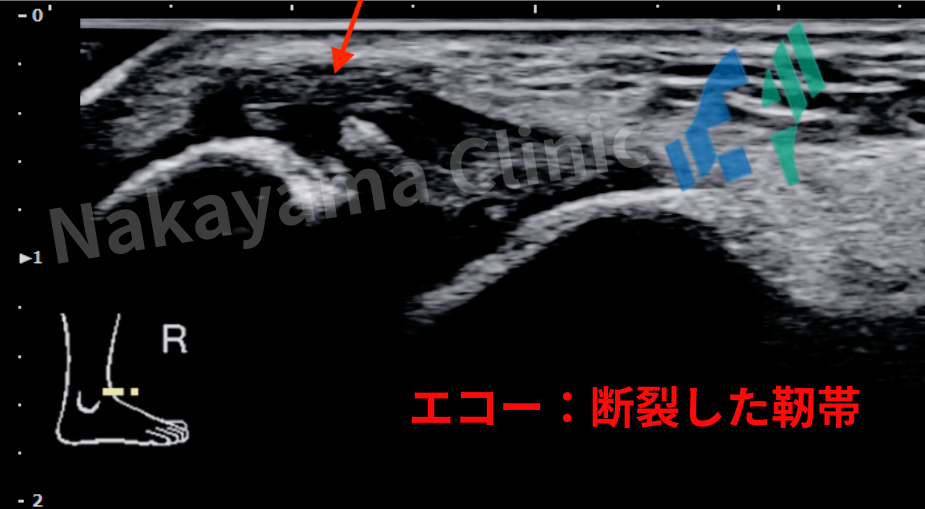

そこで必須となるのが、超音波(エコー)検査です。

当クリニックでも捻挫の診断にはエコーを積極的に用いています。

エコーなら、レントゲンでは見えない靭帯が切れているか、どの程度損傷しているか(II度かIII度か)を、

その場でリアルタイムに確認できます🫡。

さらに、レントゲンでは見えにくい小さな骨折(剥離骨折など)や、

関節の中に血が溜まっていないかなども同時に評価できます。

最新の研究では、急性の靭帯損傷の診断において、

エコーはMRIに匹敵する、あるいはそれ以上の精度を持つことが示されています[1]。